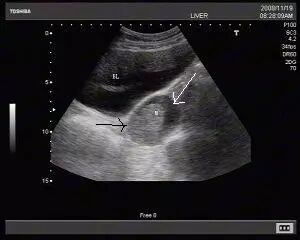

2、低回声、无回声、

边界清楚、边界不清

超声报告里通常会形容结节是“低回声”或“无回声”。在超声的黑白图像上,各种不同性质的“结节”自然有的黑一些(低回声),有的更黑一些(无回声)。“边界清楚”或“边界不清”则是形容这些“结节”在图像上是否清晰可辨。不能说“边界不清”就是恶性的,或者“边界清楚”就是良性,这还需要医师具体分析。